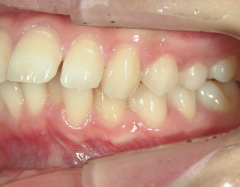

矯正歯科 治療前